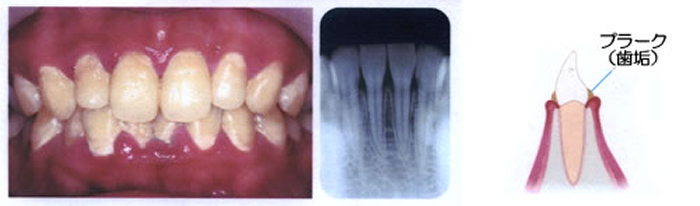

歯肉炎~軽度の歯周炎歯周病原菌

歯と歯ぐきの間にプラークがたまって歯ぐきが腫れ、出血しやすくなっています。

歯を支える骨にはまだあまり影響がありません。